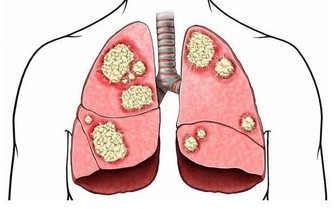

原來Josef是因為最近出現背痛、呼吸不順的症狀,才趕快赴往醫院檢查,起初他以為是肥胖因素導致身體出狀況,不過到院檢查後卻發現是肚子裡長著一顆腫瘤,大到已經擠壓到附近的器官:腎臟、肝臟與肺部,為求保命在醫生的建議下立即動手術移除腫瘤。

最後這場手術歷經六小時才成功切除腫瘤,待醫生一秤之下才知道這顆腫瘤重達27公斤。

術後的Josef仍須住院六個月積極治療,由於腫瘤與病人的腹部其他組織有相連,因此醫生也不敢大膽預測他的往後的病情會是如何,據了解,類似的大腫瘤病況在捷克境內相當罕見。